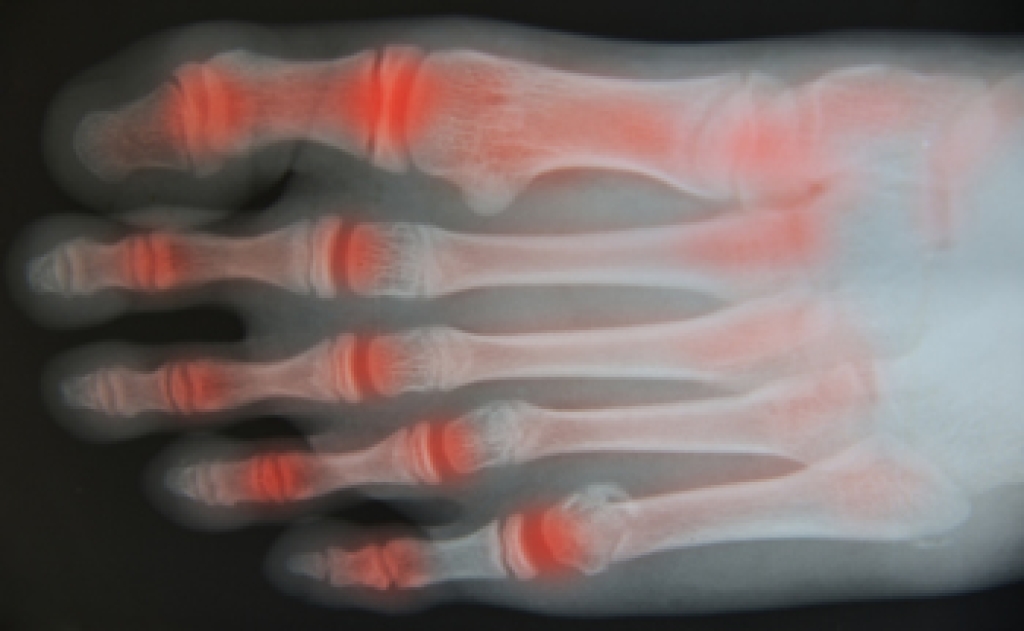

Arthritis, defined as joint inflammation, can lead to stiffness, swelling, and pain in affected joints. Among the 100 or more types of arthritis, studies have shown that three significantly impact the foot and ankle. Osteoarthritis, the most common, stems from joint cartilage wear and tear over time. Rheumatoid arthritis, or RA, is an autoimmune disease, that affects joints throughout the body, with women being twice as susceptible. RA involves the immune system attacking and damaging the cartilage. Post-traumatic arthritis, akin to osteoarthritis, can emerge years after fractures or injuries. Gout, another inflammatory condition, arises from uric acid crystal deposits that are near or within the connective tissue of the joints and is particularly common in the big toe. Psoriatic arthritis can produce symptoms that are similar to RA and is linked to psoriasis, a skin disorder causing scaling and flakiness. Understanding these types of arthritis can empower individuals to manage their foot health amidst arthritis challenges. If you believe you have developed a form of arthritis that is affecting your feet or ankles, it is suggested that you consult a podiatrist.

Arthritis is a term that is commonly used to describe joint pain. The condition itself can occur to anyone of any age, race, or gender, and there are over 100 types of it. Nevertheless, arthritis is more commonly found in women compared to men, and it is also more prevalent in those who are overweight. The causes of arthritis vary depending on which type of arthritis you have. Osteoarthritis for example, is often caused by injury, while rheumatoid arthritis is caused by a misdirected immune system.

Arthritic symptoms range in severity, and they may come and go. Some symptoms stay the same for several years but could potentially get worse with time. Severe cases of arthritis can prevent its sufferers from performing daily activities and make walking difficult.